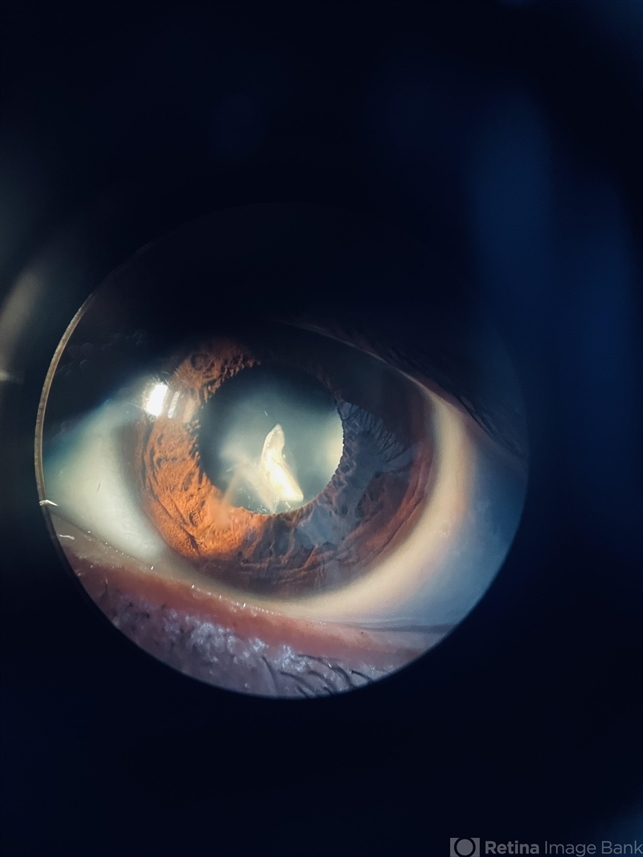

- intraocular foreign body

- intralenticular foreign body

Photo slit lamp biomicroscope

Iphone 12 - Description

- Clinical Photograph in a 29-year-old male with an intralenticular metallic foreign body in the left eye